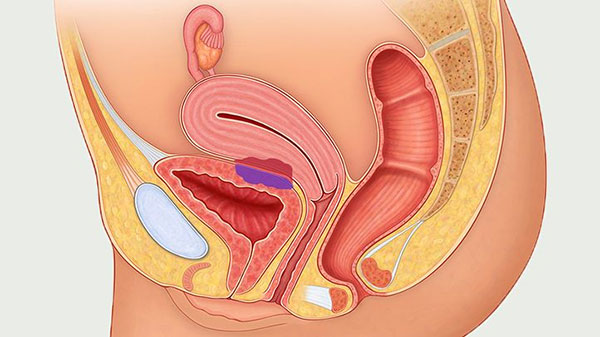

برای بررسی دقیقتر اندامهای داخلی لگن، از روشهای تصویربرداری مانند سونوگرافی استفاده میشود. این روش بر پایه امواج صوتی با فرکانس بالا است که با استفاده از ابزاری به نام مبدل، تصاویری از درون بدن ایجاد میکند. مبدل ممکن است یا روی شکم قرار بگیرد (سونوگرافی شکمی) یا داخل واژن وارد شود (سونوگرافی ترانسواژینال). در برخی موارد، برای دقت بالاتر، هر دو نوع سونوگرافی به طور همزمان یا پشتسرهم انجام میشوند تا دید جامعتری از اندامهای تناسلی فراهم شود.

اندومتریوز معمولاً به سطوح صفاقی یا سروزی اندامهای لگنی، معمولاً تخمدانها، رباطهای پهن، کولدساک خلفی و رباطهای رحمی خاجی محدود میشود.

محل های کمتر شایع شامل لوله های فالوپ، سطوح سروزی روده کوچک و بزرگ، حالب، مثانه، واژن، دهانه رحم، اسکارهای جراحی و به ندرت ریه، پلور و پریکارد می باشد.

آندومتریوز با وجود بافت آندومتر در خارج از رحم، یعنی روی تخمدانها، لولههای فالوپ، رباطهای ساکرال رحم (رباطهایی که از رحم حمایت میکنند)، صفاق، مثانه، روده و به ندرت ریهها و حتی مغز مشخص میشود.